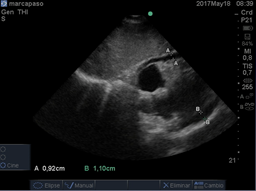

El diagnóstico de derrame pericárdico en paciente para colocación de marcapasos se realiza inicialmente con ecocardiografía transtorácica (ETT), (Figura f)